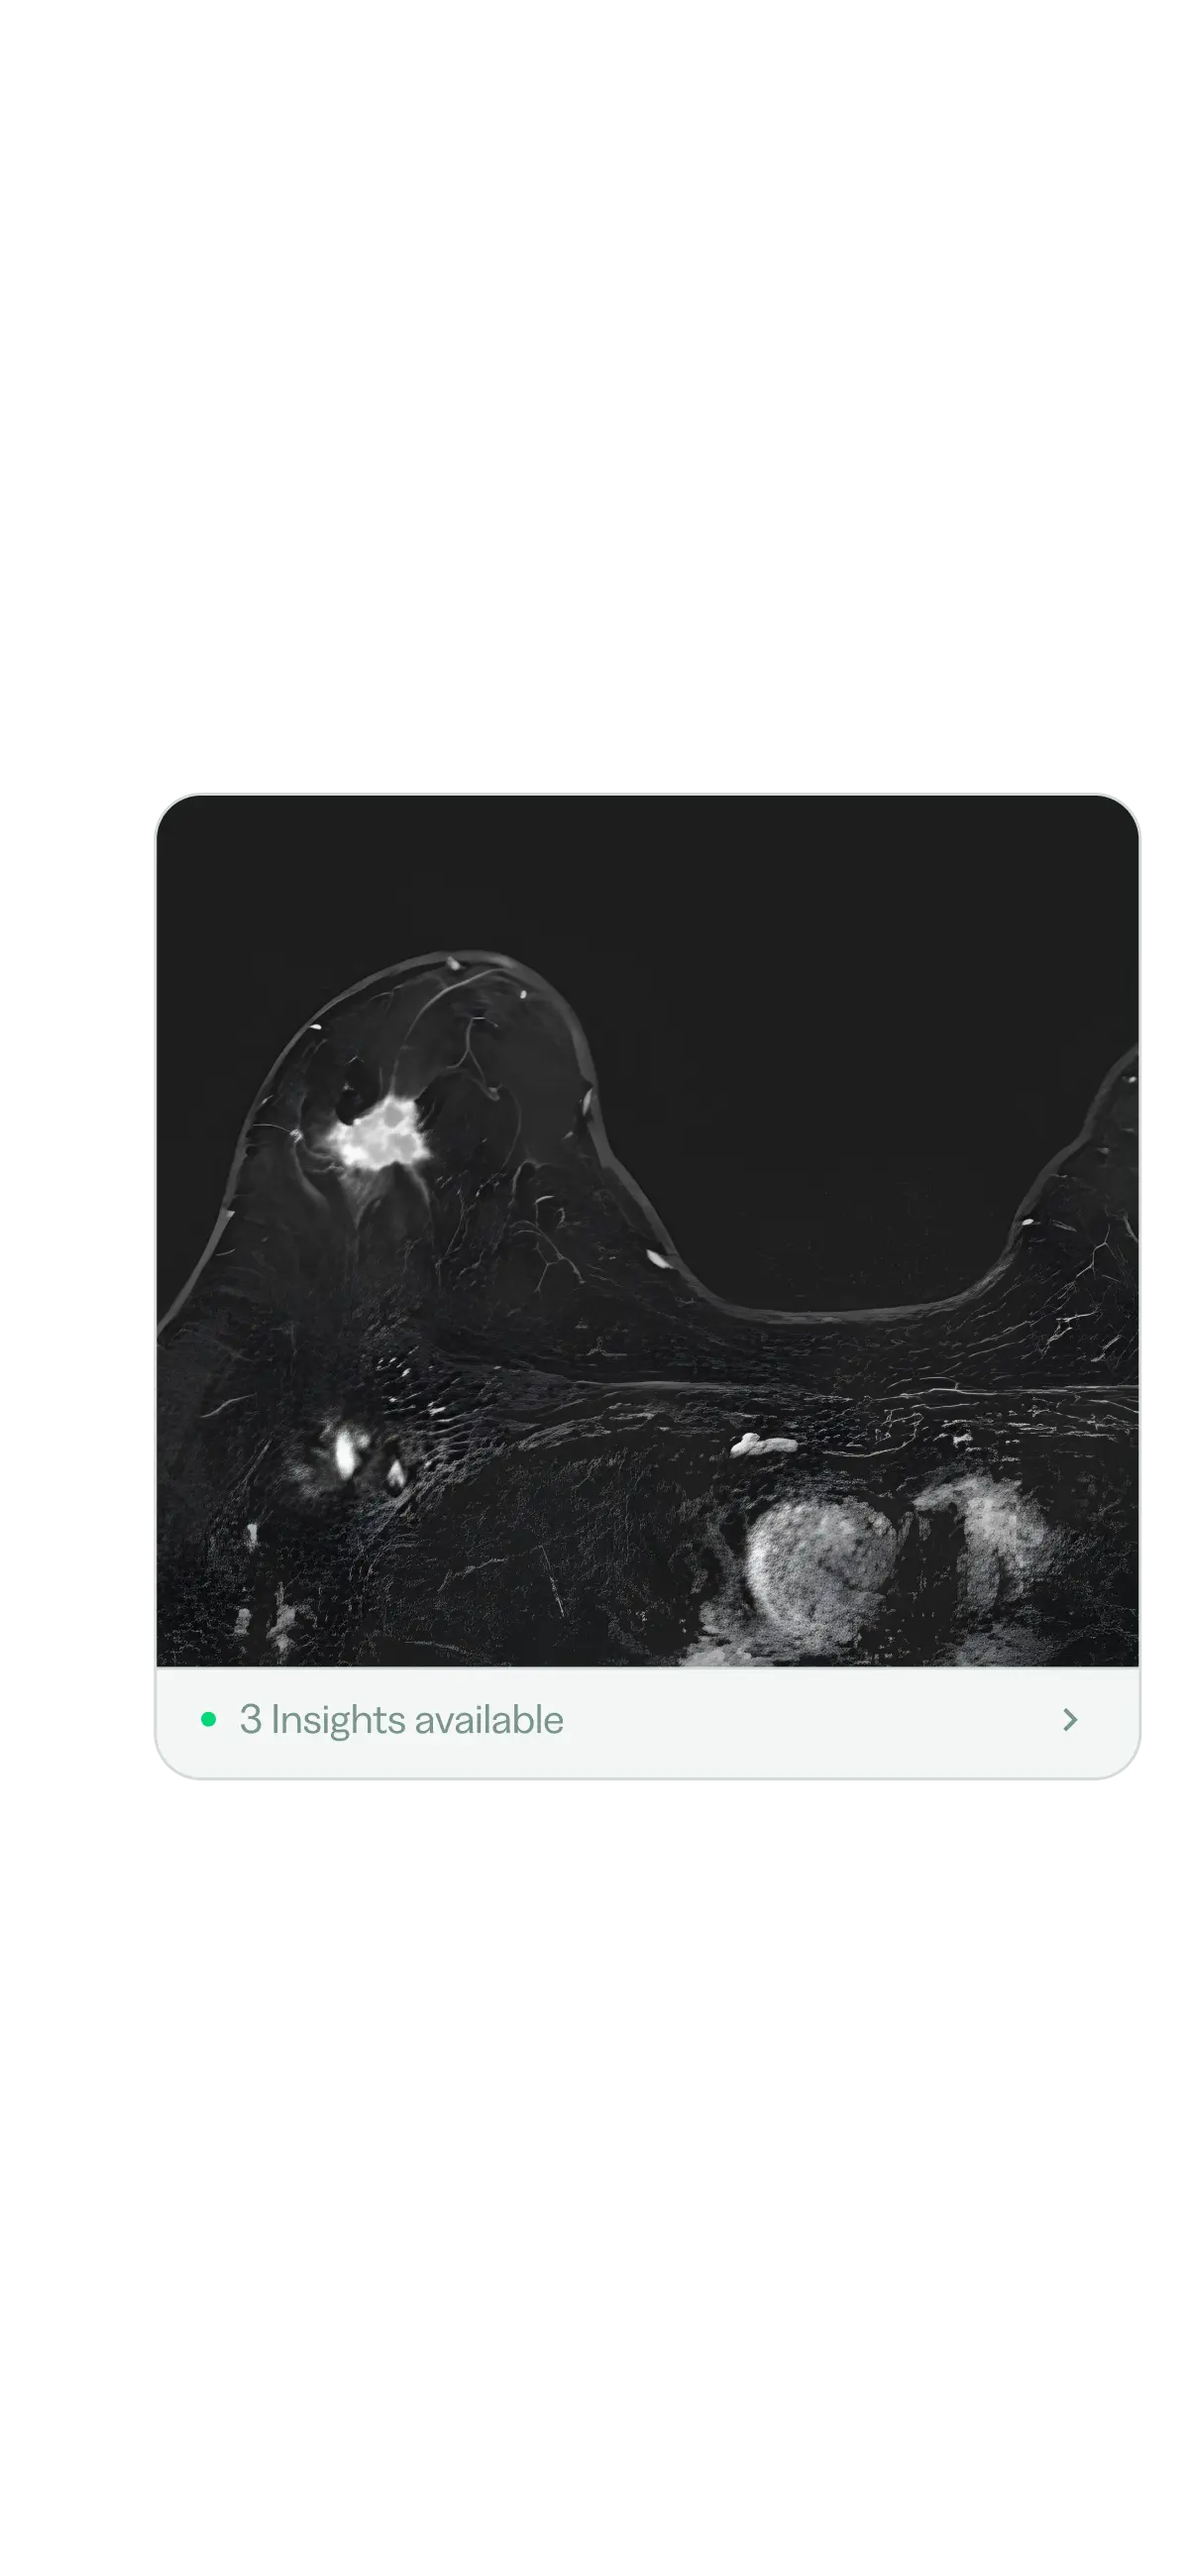

Need empowers you with advanced radiology

tooling to make the best decisions